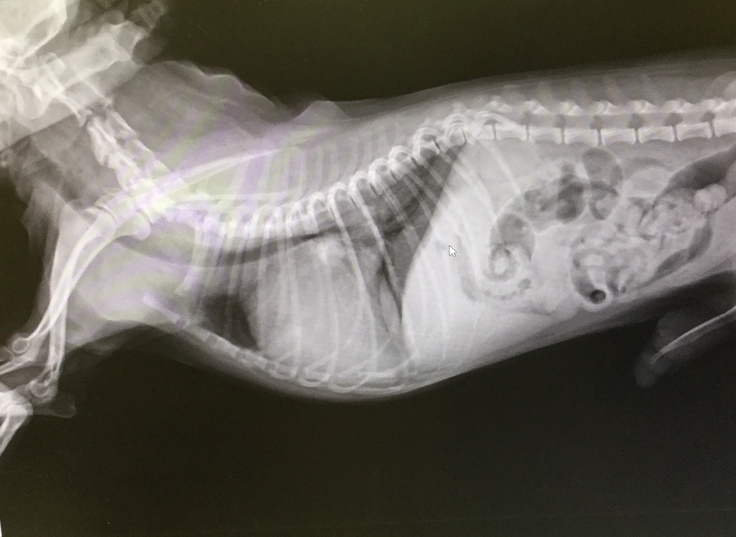

こちらは9月11日の心臓検査の診察結果です。写真を比較していただくと、心臓が大きく肥大しており気管を圧迫しているのが分かります。

肥大したろんの心臓

現在ステージCです。Dまで到達すると手術ができなくなってしまいます。

右の画像は心臓の弁膜が伸びて腱が切れている状態

左の画像は心臓の血液のほとんどが逆流している状態

↑10月8日の心臓の検査でさらに心臓が肥大している事が分かりました。